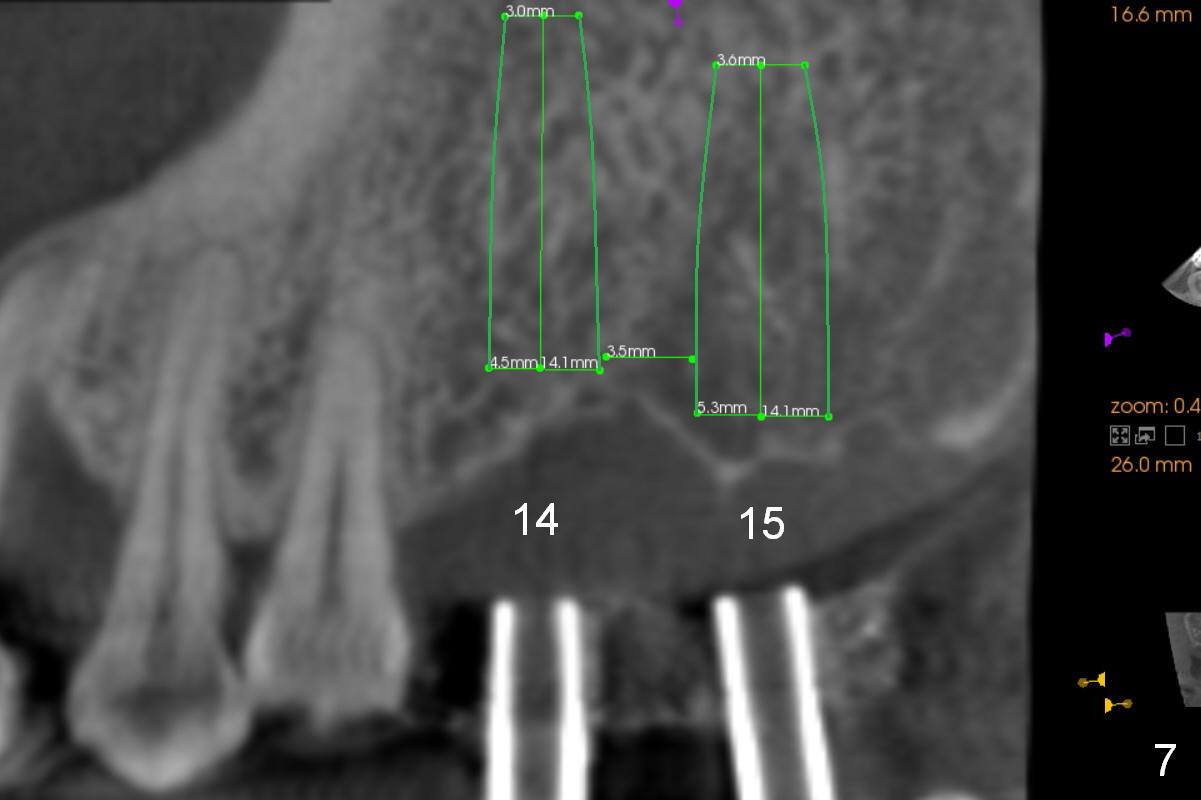

A 52-year-old man has multiple missing teeth. Since he has a lower partial denture (Fig.5), implants will be placed at the sites of #14 and 15 first (Fig.1). The site of #14 may need bone expansion if bone density is low, whereas the ridge at #15 is wide (Fig.2). There is no problem in height at the sites of #14 and 15 (Fig.3).

CBCT confirms that the ridge at #14 is narrower than that at #15. In contrast, the bone density is lower at #15 than that at #14 (Fig.7-9). If the keratinized tissue is wide, use 4 mm tissue punch (3 mm from #13). If incision is made, wheel saws will be used to split the ridge. Or use Magic split and osteotomes. Bone expanders are going to be used for bone expansion at #14 and bone condensation at #15 (Fig.8,9). Be careful while using bone expanders at #14, since the bone density is higher. There is a chance of plate fracture. Use drills if indicated. Fabricate splinted provisional after placement of abutments.